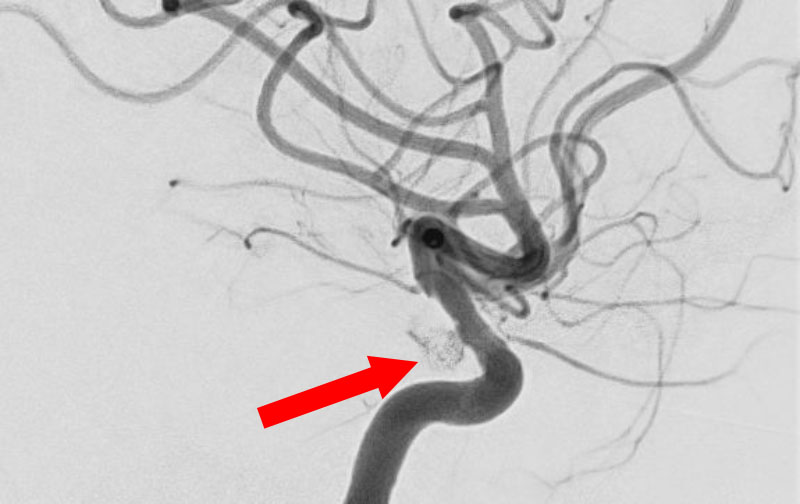

No.1631 手術中